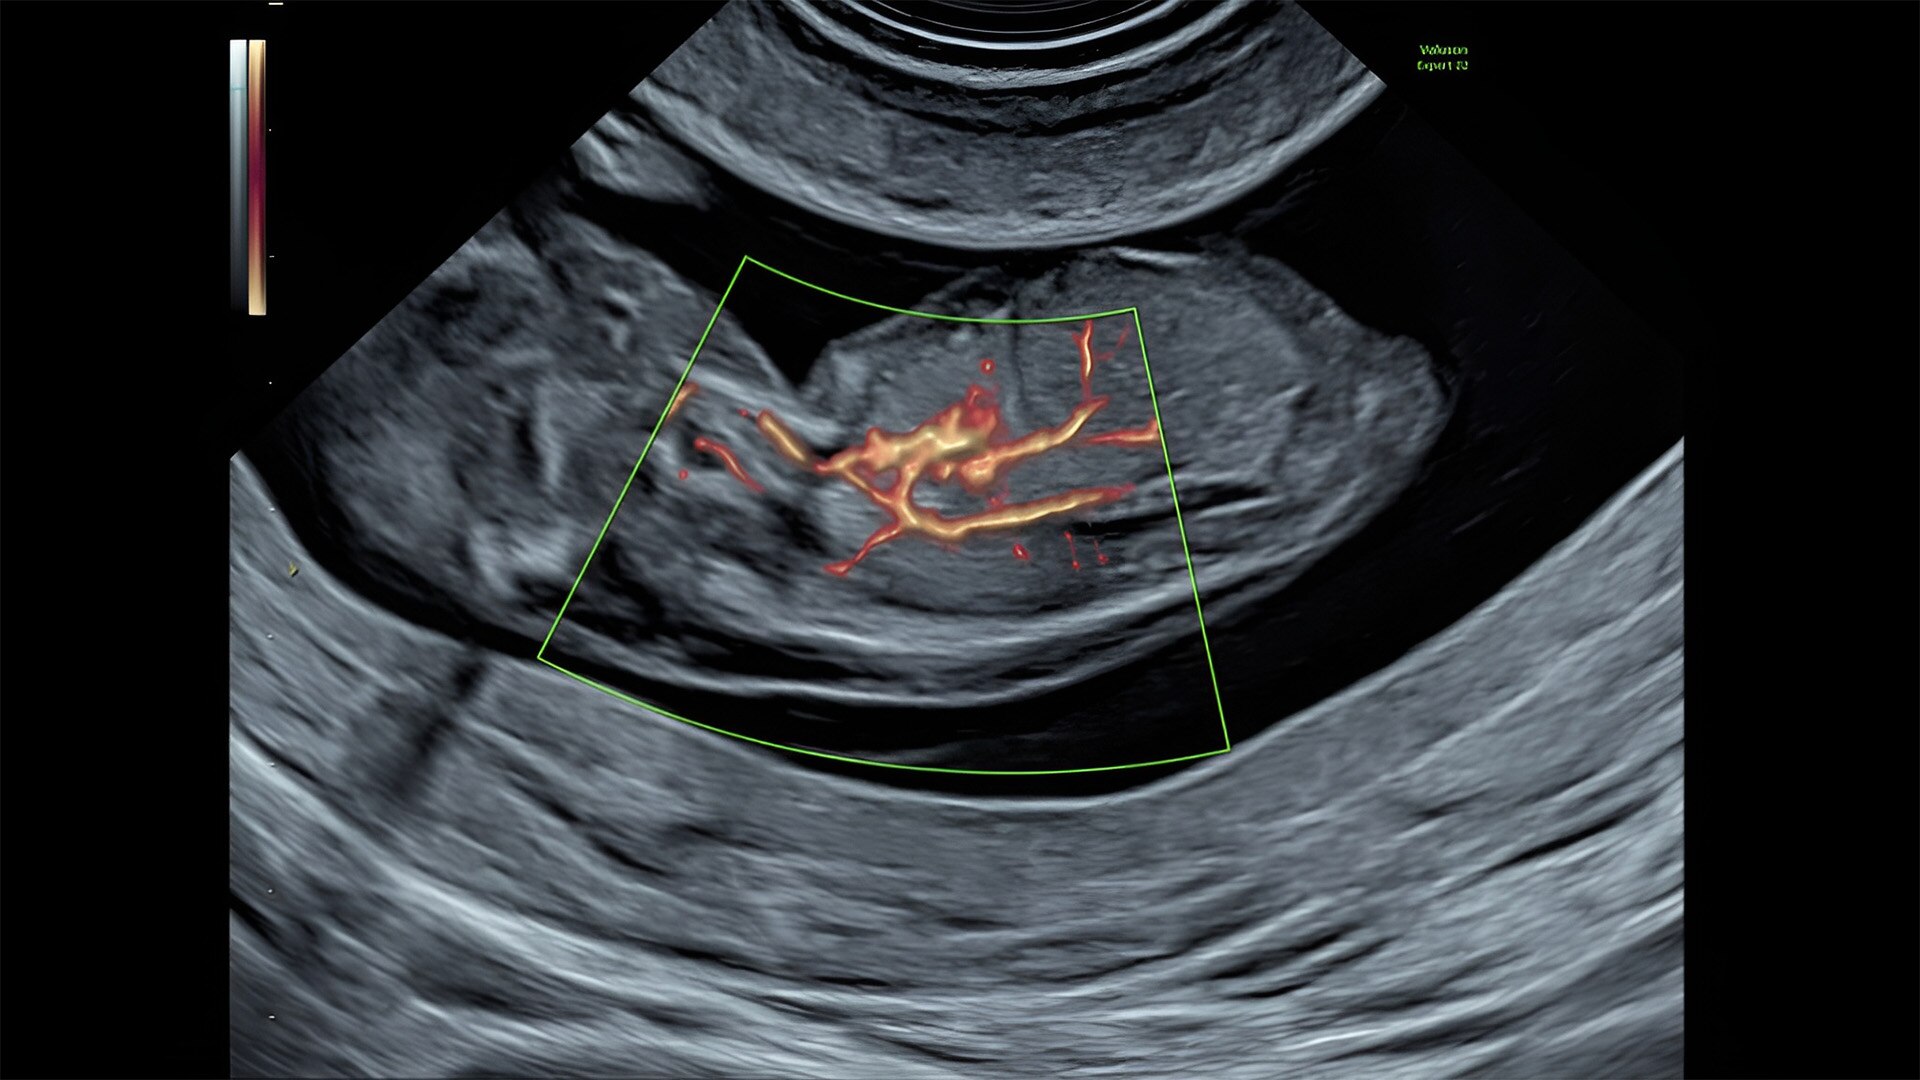

Fetal heart assessment

Detect, diagnose, and monitor with confidence using Radiant and fetalHQ

Fetal heart evaluation

Get to the heart of the matter

Identifying fetal cardiac abnormalities earlier means you can intervene sooner, plan for delivery, and potentially improve outcomes. The Voluson Expert 22 provides a full solution of progressive tools, to help distinguish the tiniest structures with stunning clarity to provide patient answers faster.